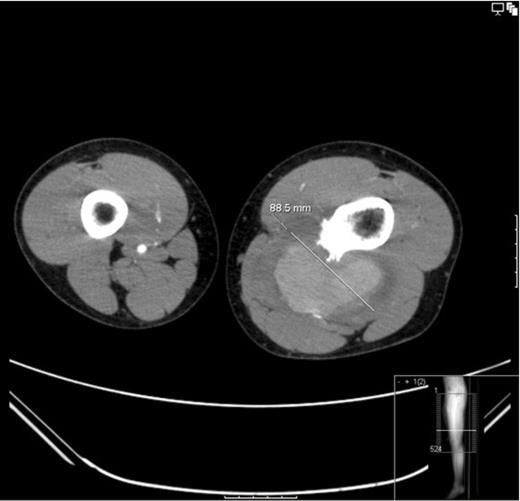

An ultrasound concluded an 8.8cm pseudoaneurysm and the patient was admitted for urgent pre-op CT angio (figure 3 and 4) and surgical exploration.

CT angiogram: Showing the diameter size of the aneurysm to be 88.6mm. The cross sectional image clearly shows the sharp bony exostoses that slowly eroded into the popliteal artery resulting in the pseudoaneurysm formation. The image also shows that the defect in the artery is still patent because the pseudoaneurysm is filling with contrast